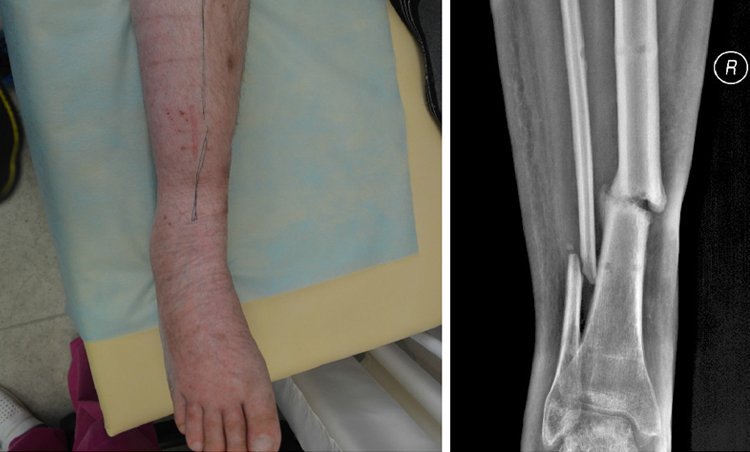

Волинський боєць 51 ОМБр, який підірвався на міні поблизу Слов'янська, переніс операцію та пройшов тривалу реабілітацію, досі не може стати на ноги. Герой потребує біотехнічної реабілітації.

Волинянина Юрія у квітні 2014 року з рівненського полігону направили на схід. 4 липня 2014 року він їхав за боєприпасами і в одну хвилину небо змінило землю – потужним вибухом бійця викинуло з кабіни. Єдине насьогодні бажання 25-річного Юри – це стати на ноги і відкинути вже остогидлі за рік милиці.

Того ж дня в Харкові йому зробили операцію - зашивали відкритий перелом. За тиждень відправили у Вінницю. Там вже поставили апарат, вирівняли кістки, дістали уламок з голови, днів через десять шви познімали і відправили додому - у Нововолинськ.